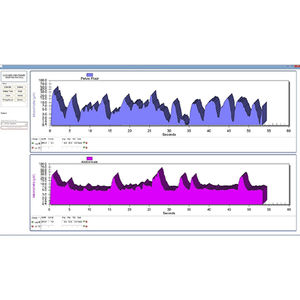

... SOFTWARE TELESIS® PARA LA SERIE PATHWAY® MR Incluye una unidad flash USB del software Telesis® para la serie Pathway® MR, un cable de interfaz serie USB, una guía del operador del software Telesis® para ...

... SOFTWARE TELESIS® ST PARA LA SERIE PATHWAY® MR Incluye una unidad flash USB del software Telesis® para la serie Pathway® MR, un cable de interfaz serie USB, una guía del operador del software Telesis® ...